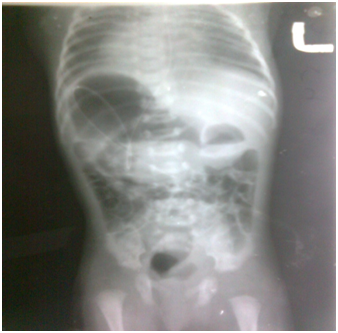

1. X-ray erect abdomen including chest showed situs in versus totalis (Figure 6).

Figure 6 Xray chest with abdomen showing situs inversus totalis.